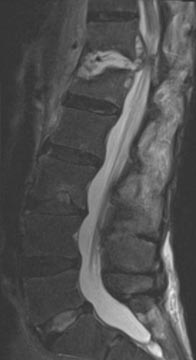

61 year old man with previous history of microdiscectomy at L4-5 presenting with severe back pain with radiating pain down the right leg with weakness. He had a massive disc extrusion on the right side. Options included revision discectomy vs. L4-5 revision decompression and fusion with transforaminal lumbar interbody fusion (TLIF). Patient did not want to go through the pains of recurrent disc herniation again and elected for the fusion.